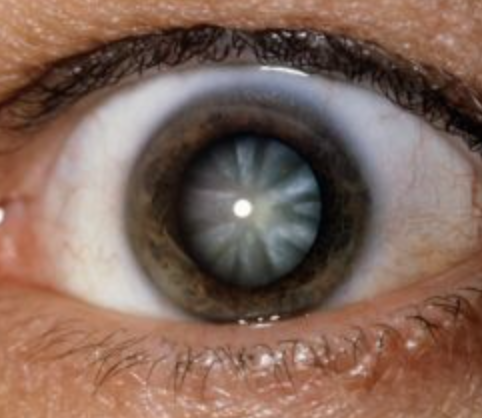

Cataracts

Abnormal Finding for 10. Inspect the cornea and lens

Opacities of the lens

Nuclear Cataract

Nuclear Cataract

One of the 4 Lens Abnormalities

Appear gray when seen with a flashlight

Appear as a black spot against the red reflex when seen through an opthalmoscope